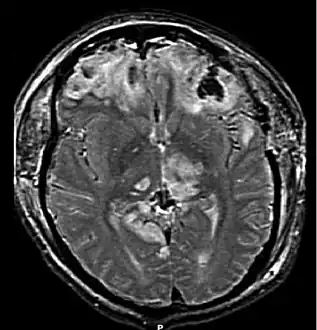

Magnetic resonance imaging (MRI) can show more detail than CT, and can add information about expected outcome in the long term.[32] It is more useful than CT for detecting injury characteristics such as diffuse axonal injury in the longer term.[27] However, MRI is not used in the emergency setting for reasons including its relative inefficacy in detecting bleeds and fractures, its lengthy acquisition of images, the inaccessibility of the patient in the machine, and its incompatibility with metal items used in emergency care.[32] A variant of MRI since 2012 is High definition fiber tracking (HDFT).[81]

Diffuse injury manifests with little apparent damage in neuroimaging studies, but lesions can be seen with microscopy techniques post-mortem,[94][95] and in the early 2000s, researchers discovered that diffusion tensor imaging (DTI), a way of processing MRI images that shows white matter tracts, was an effective tool for displaying the extent of diffuse axonal injury.[96][97] Types of injuries considered diffuse include edema (swelling), concussion and diffuse axonal injury, which is widespread damage to axons including white matter tracts and projections to the cortex.[98][99]